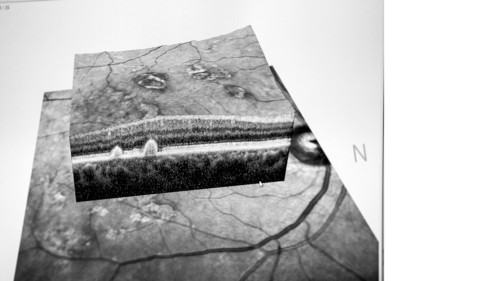

Glaucoma is a major cause of irreversible blindness, marked by progressive damage to the optic nerve. Mutations observed in OPTN, TBK1, MYOC, CYP1B1 genes among others have been reported to cause abnormal protein accumulation in the trabecular meshwork.

Your space to connect: The Macular degeneration Hub

A new Communities’ space to connect, collaborate, and explore research on Ophthalmology and Eye Diseases!